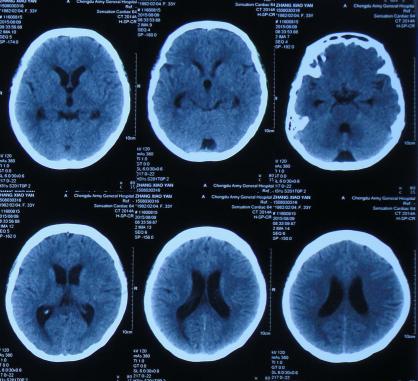

经头孢哌酮舒巴坦抗感染治疗1周后即2015年8月9日,仍间断头痛,发热有下降,但仍反复,但患者意识反变差,表情也变淡漠,查头部CT(图-2)。

图-2:2015年8月9日头部CT

第1家医院治疗13天后即2015年8月16日,查头CT:双侧侧脑室,三脑室及四脑室扩张(图-4),且给予腰穿检查,提示颅压高(脑脊液检查结果不详),给予相关对症治疗。

图-4:2015年8月16日头部CT